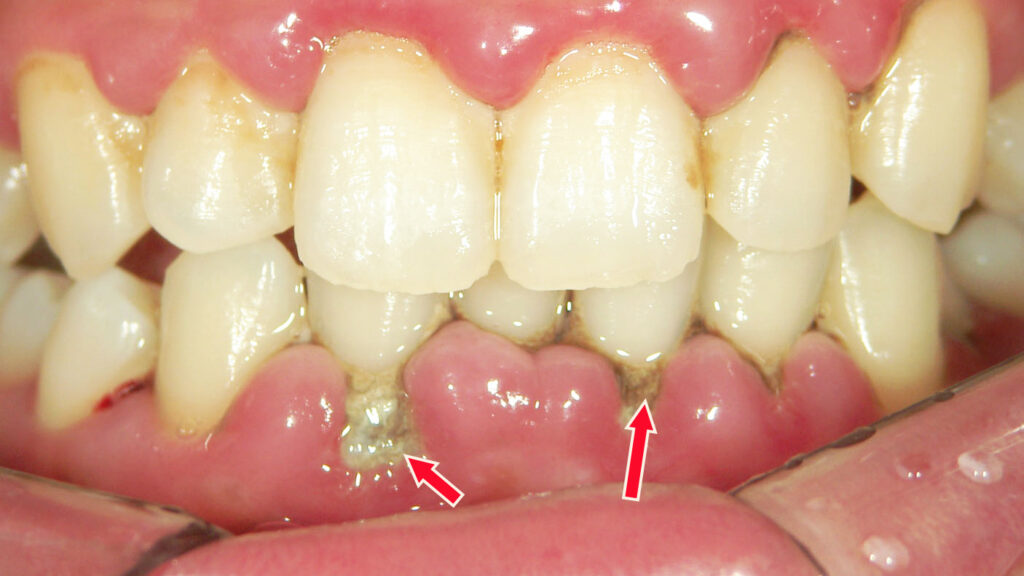

🦷 ⚫黒い歯石(歯肉縁下歯石)

🦴 黒い歯石(歯肉縁下歯石)の特徴とは?

- 黒い歯石が見える理由

→ 本来は歯茎の中にできる歯石ですが、歯周病により歯茎が下がると外に露出します。 - 下顎前歯に多く見られる沈着

→ 表面に黒い歯石が大量に付着しているのは、歯周病がかなり進行しているサイン。 - 黒い歯石を除去する際の注意点

→ 除去によってさらに歯茎が下がる可能性があるため、慎重な処置が必要。

⚠️ 黒い歯石と虫歯の併発

- 歯磨き不足による虫歯の発生

→ 上顎の複数の歯にも虫歯が見られ、セルフケアの不十分さが目立ちます。

📸 症例:重度歯周病による歯石露出

- 歯茎の炎症と腫れ

→ 歯茎が丸く腫れており、歯周病による炎症が進行中。 - 歯茎の裂開と歯石の露出

→ 歯茎の裂け目から、黒い歯石が歯の表面に出てきている状態。 - レントゲン所見:歯槽骨の破壊

→ 歯周病による影響で、歯を支える骨がかなり失われていることが確認されました。

このレントゲンは、重度歯周病が進行した部位に特徴的な 縁下歯石(青い矢印) と、高度な歯槽骨吸収(赤い矢印) がはっきりと読み取れる症例です。